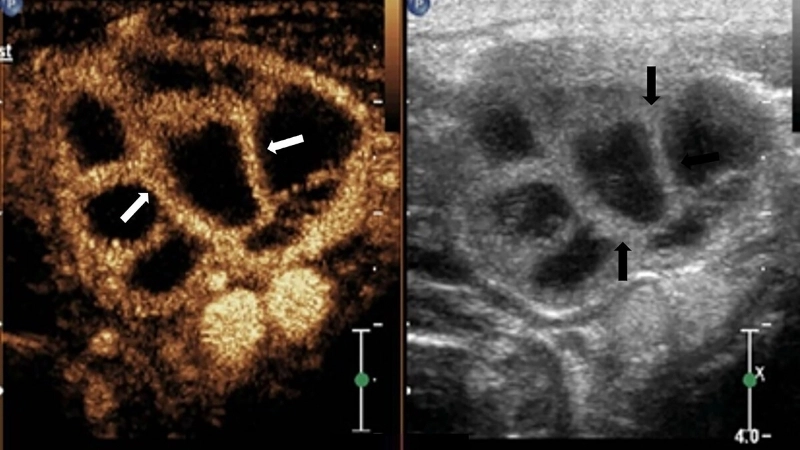

Hình ảnh siêu âm giúp phát hiện các hạch lao